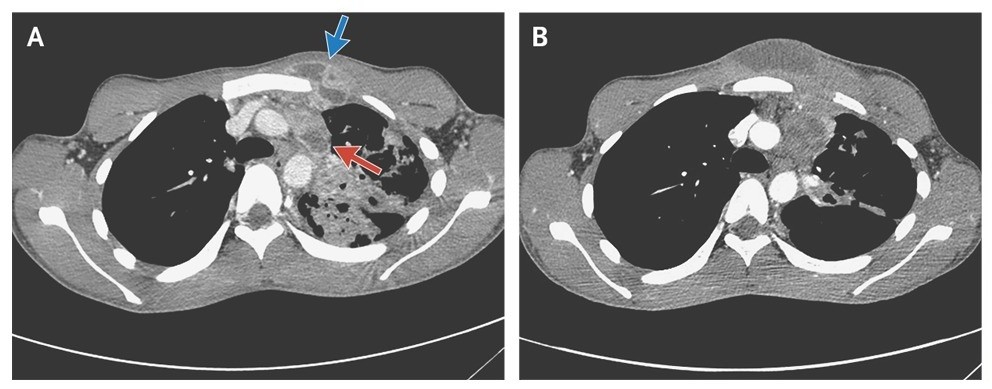

The patient received 8 weeks of standard antituberculous treatment, but the infection progressed, with increased swelling, erythema, and fluctuation of the subcutaneous abscess (Panels B). The abscess was subsequently treated with open drainage.